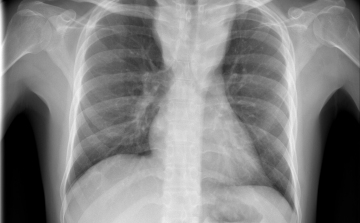

Terjed a tbc Szatymazon?

Hétfő reggel óta tbc-tesztet végeznek el a gyerekeken egy szatymazi általános iskolában, ahol egy hete fertőző tüdőbetegségben halt meg egy korábban ott dolgozó nő - közölték az M1 aktuális csatorna déli Híradójában.

Csökkent a tbc-fertőzések száma Európában

Átlagosan 4,3 százalékkal csökkent az új tuberkulózisos (tbc-s) esetek száma 2010 és 2014 között az Egészségügyi Világszervezet (WHO) 53 országot magába foglaló európai régiójában.

A tuberkulózis, a kanyaró, a HIV és a rezisztens baktériumok terjedése aggodalomra adhat okot Európában – állapították meg a régió járványügyi szervezetének (ECDC) éves jelentésében.

40 millió dohányos halhat meg tbc-ben 2050-ig